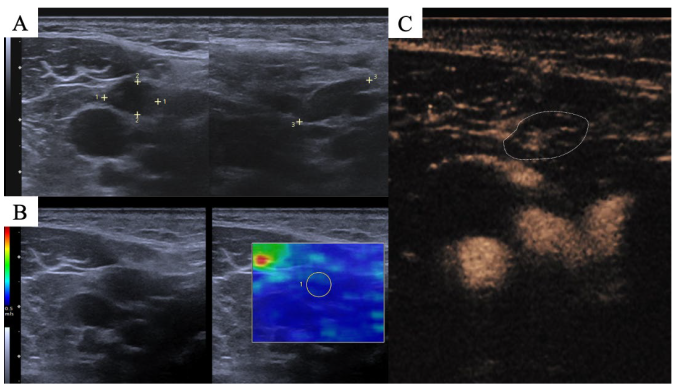

2.2. Imaging Protocol

2.3. Image Interpretation